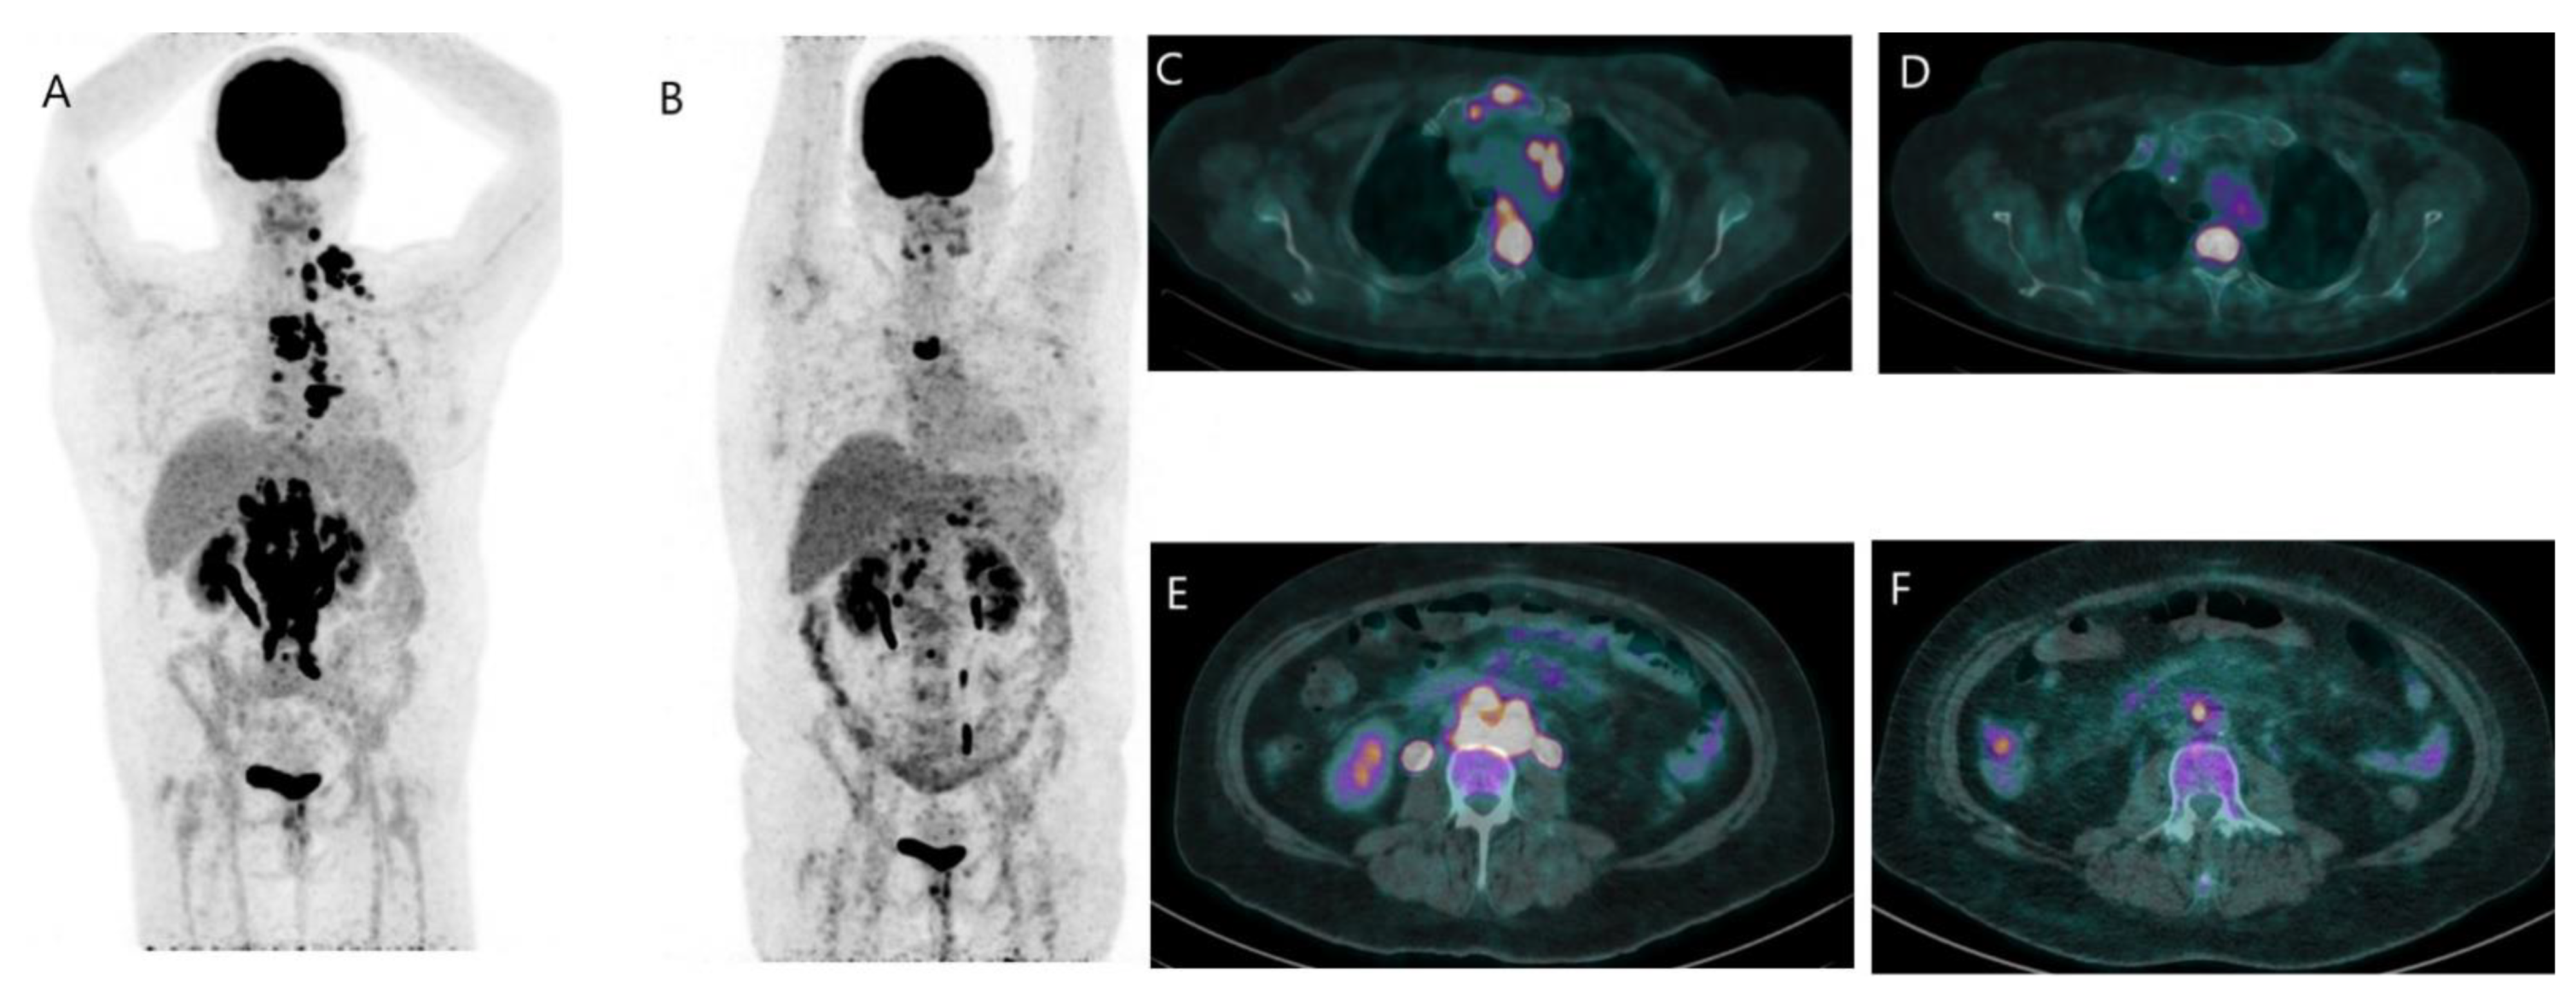

2.3.1. Metastatic Disease

- Hildebrandt, M.G.; Naghavi-Behzad, M.; Vogsen, M. A role of FDG-PET/CT for response evaluation in metastatic breast cancer? Semin. Nucl. Med. 2022, 52, 520–530. [Google Scholar] [CrossRef]